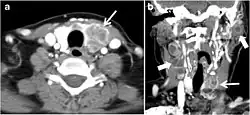

Fig. 5. A poorly differentiated invasive left thyroid mass in a 58-year-old female patient. a Sagittal greyscale neck ultrasound shows a large hypoechoic lesion with macro-calcification and micro-calcification. b Sagittal colour Doppler ultrasound shows left internal jugular vein filling defect with detected internal vascularity suggestive of tumour thrombus. c Enhanced axial and coronal CT scans of the neck show heterogeneously enhancing large lesion replacing the left thyroid lobe and extending to the isthmus and the medial aspect of the right thyroid lobe (white arrow). The mass and the conglomerate lymph nodes measure 12.5 × 7 × 5.8 cm (white arrows). d, e Axial enhanced CT scans show enlarged left cervical nodes (white arrow) and left internal jugular vein (IJV) thrombus (black arrows). Note the IJV distention and central enhancing portion in the upper cut (black arrow in e) concerning the tumour thrombus. f, g Enhanced axial CT scan of the upper chest demonstrate a mass extension into the retrosternal area, left tracheoesophageal groove, and posterior to the trachea (white arrows in f). There are multiple bilateral pulmonary nodules (white arrows in g).[1]